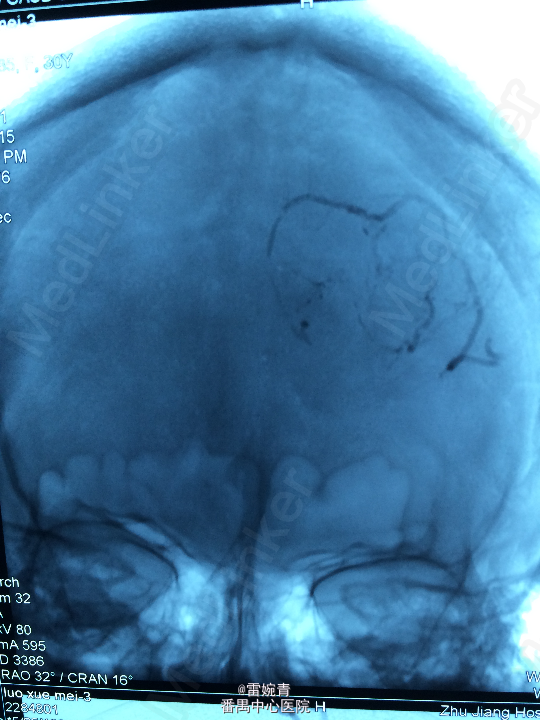

诊断:脑膜瘤 处理:先行DSA检查以明确脑膜瘤的供血动脉情况,见:肿瘤染色,肿瘤主要由左侧眼动脉供血,用Glubran胶将其闭塞,后择期行手术切除治疗。术后病理证实为脑膜瘤。